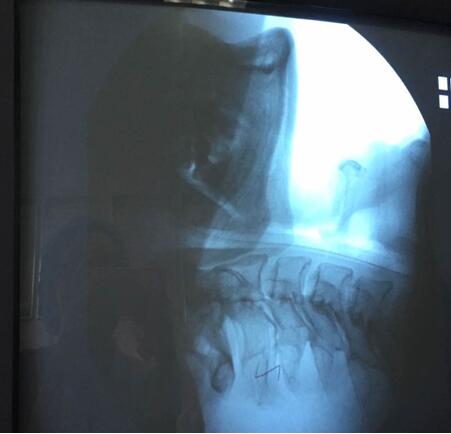

吞咽造影檢查,是在X線透視下,針對(duì)口、咽、食管的吞咽運(yùn)動(dòng)所進(jìn)行的特殊造影,此項(xiàng)檢查可以進(jìn)行點(diǎn)片或錄像來(lái)記錄所看到的影響,并加以分析。通過(guò)吞咽造影檢查,臨床上可以明確患者是否存在吞咽障礙,可以發(fā)現(xiàn)吞咽障礙的結(jié)構(gòu)性或功能性異常的病因及其部位、程度和代償情況,吞咽障礙發(fā)生在哪個(gè)時(shí)期,有無(wú)誤吸,尤其是會(huì)并發(fā)肺炎的高度危險(xiǎn)的隱形誤吸,嚴(yán)重程度如何,評(píng)價(jià)代償?shù)挠绊懀瑸檫x擇有效治療措施(進(jìn)食姿態(tài)治療和姿勢(shì)治療)和觀察治療效果提供依據(jù)。因此,吞咽造影檢查被認(rèn)為是診斷吞咽障礙首選和理想的方法,常被認(rèn)為是評(píng)價(jià)吞咽障礙的“金標(biāo)準(zhǔn)”,對(duì)指導(dǎo)臨床吞咽治療工作具有重要意義。

該患者于6月23日在山東濰坊因腦干梗死出現(xiàn)吞咽功能減退,并在當(dāng)?shù)匾患裔t(yī)院進(jìn)行檢查與治療,之后轉(zhuǎn)入我院進(jìn)行診治,經(jīng)過(guò)詳細(xì)的資料查詢和反復(fù)思索,我院康復(fù)醫(yī)學(xué)科責(zé)任總治療師梁莉娜大膽提出開(kāi)展吞咽造影檢查的設(shè)想,隨即與介入導(dǎo)管室積極協(xié)調(diào),制定了詳細(xì)的實(shí)施方案,于7月14日順利完成檢查。最終,初步檢查造影結(jié)果為吞咽障礙(咽期)、誤吸、環(huán)咽肌不完全開(kāi)放。